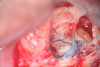

Fig 16. 3-mm root resection with methylene blue staining.

Figure 16